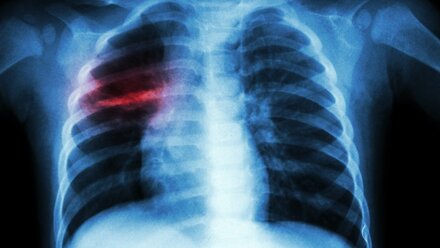

Массовое заболевание туберкулезом – ложь: керчан призвали не паниковать

В социальных сетях распространили информацию о том, что в школе №1 им. В. Дубинина, якобы зафиксированы массовые случаи заболеваемости открытой формой туберкулеза от одного из учителей. В одних сообщениях называют количество заболевших детей – 20, в других – 2.

В школе действительно подтвержден факт заболеваемости одного учащегося, ребенок находится на лечении. Об этом на своей странице в Facebook сообщил глава администрации Керчи Сергей Бороздин.

«Информация о двадцати заболевших не соответствует действительности. Школа работает в штатном режиме, проведена дезинфекция учебного учреждения. Здоровью учащихся ничего не угрожает», - заявил он.